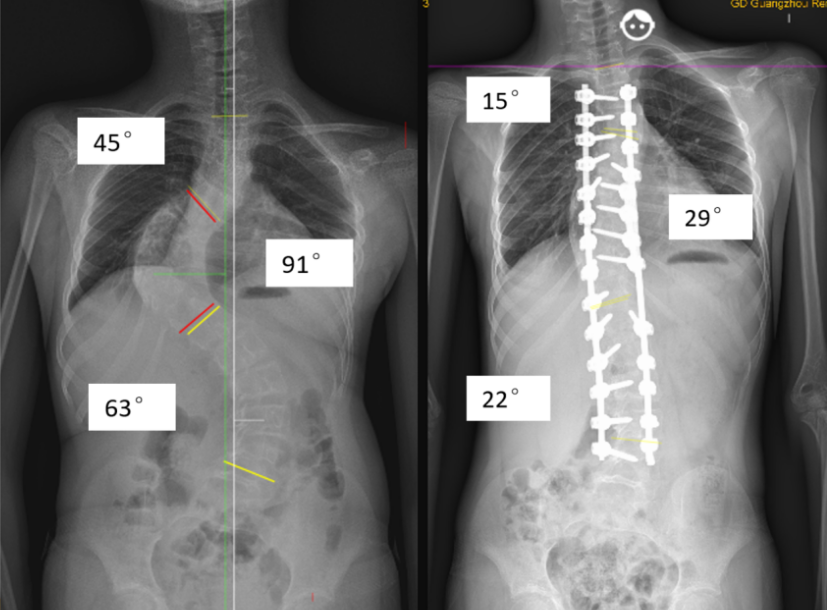

经过充分的检查以及三周的术前牵引治疗后,骨科组织了麻醉科、输血科、儿科、营养科、放射科等多学科会诊,制定拟手术方案为胸3-腰4置钉融合,胸9、腰3椎体去旋转以及顶椎区域局部椎体截骨。三周的术前牵引,令弯曲有较好的改善,其后就按原方案,运用椎体去旋转技术,置入了共27枚螺钉。这个手术用了5个小时,顺利完成,小林转入了ICU留观后,次日就转回了普通病房。

经过医护团队的悉心照顾,术后10天小林已经可以下地活动了,X光片复查结果显示,主胸弯改善68%,腰弯改善65%,身高还从术前的145厘米长高到了153厘米。

术后侧弯得到明显矫正,小林身高增长了8厘米。

“小林在去年首次发现脊柱侧弯时只有39度,当时是可以保守治疗的,但是由于海南气候太炎热,没有正确佩戴矫治支具,以至于病情进展很快,到今年4月时已经是79度和84度,只能通过手术矫正了。”缪海雄主任医师告诉记者,这也是该院收治过的最严重的脊柱侧弯患者,希望大家能通过这个病例对脊柱侧弯有更多了解,毕竟手术存在脊髓损伤、出血等风险,早期发现、早期处理会更妥当,不要等症状出现时再去做手术纠正。